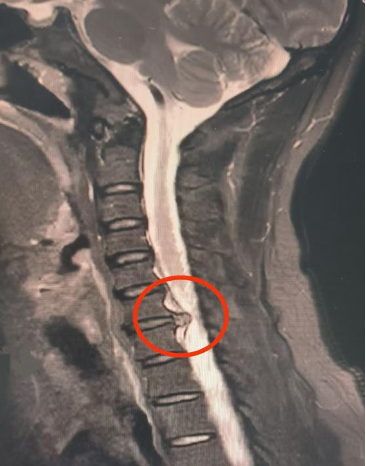

颈6/7椎间盘巨大突出压迫脊髓和神经。